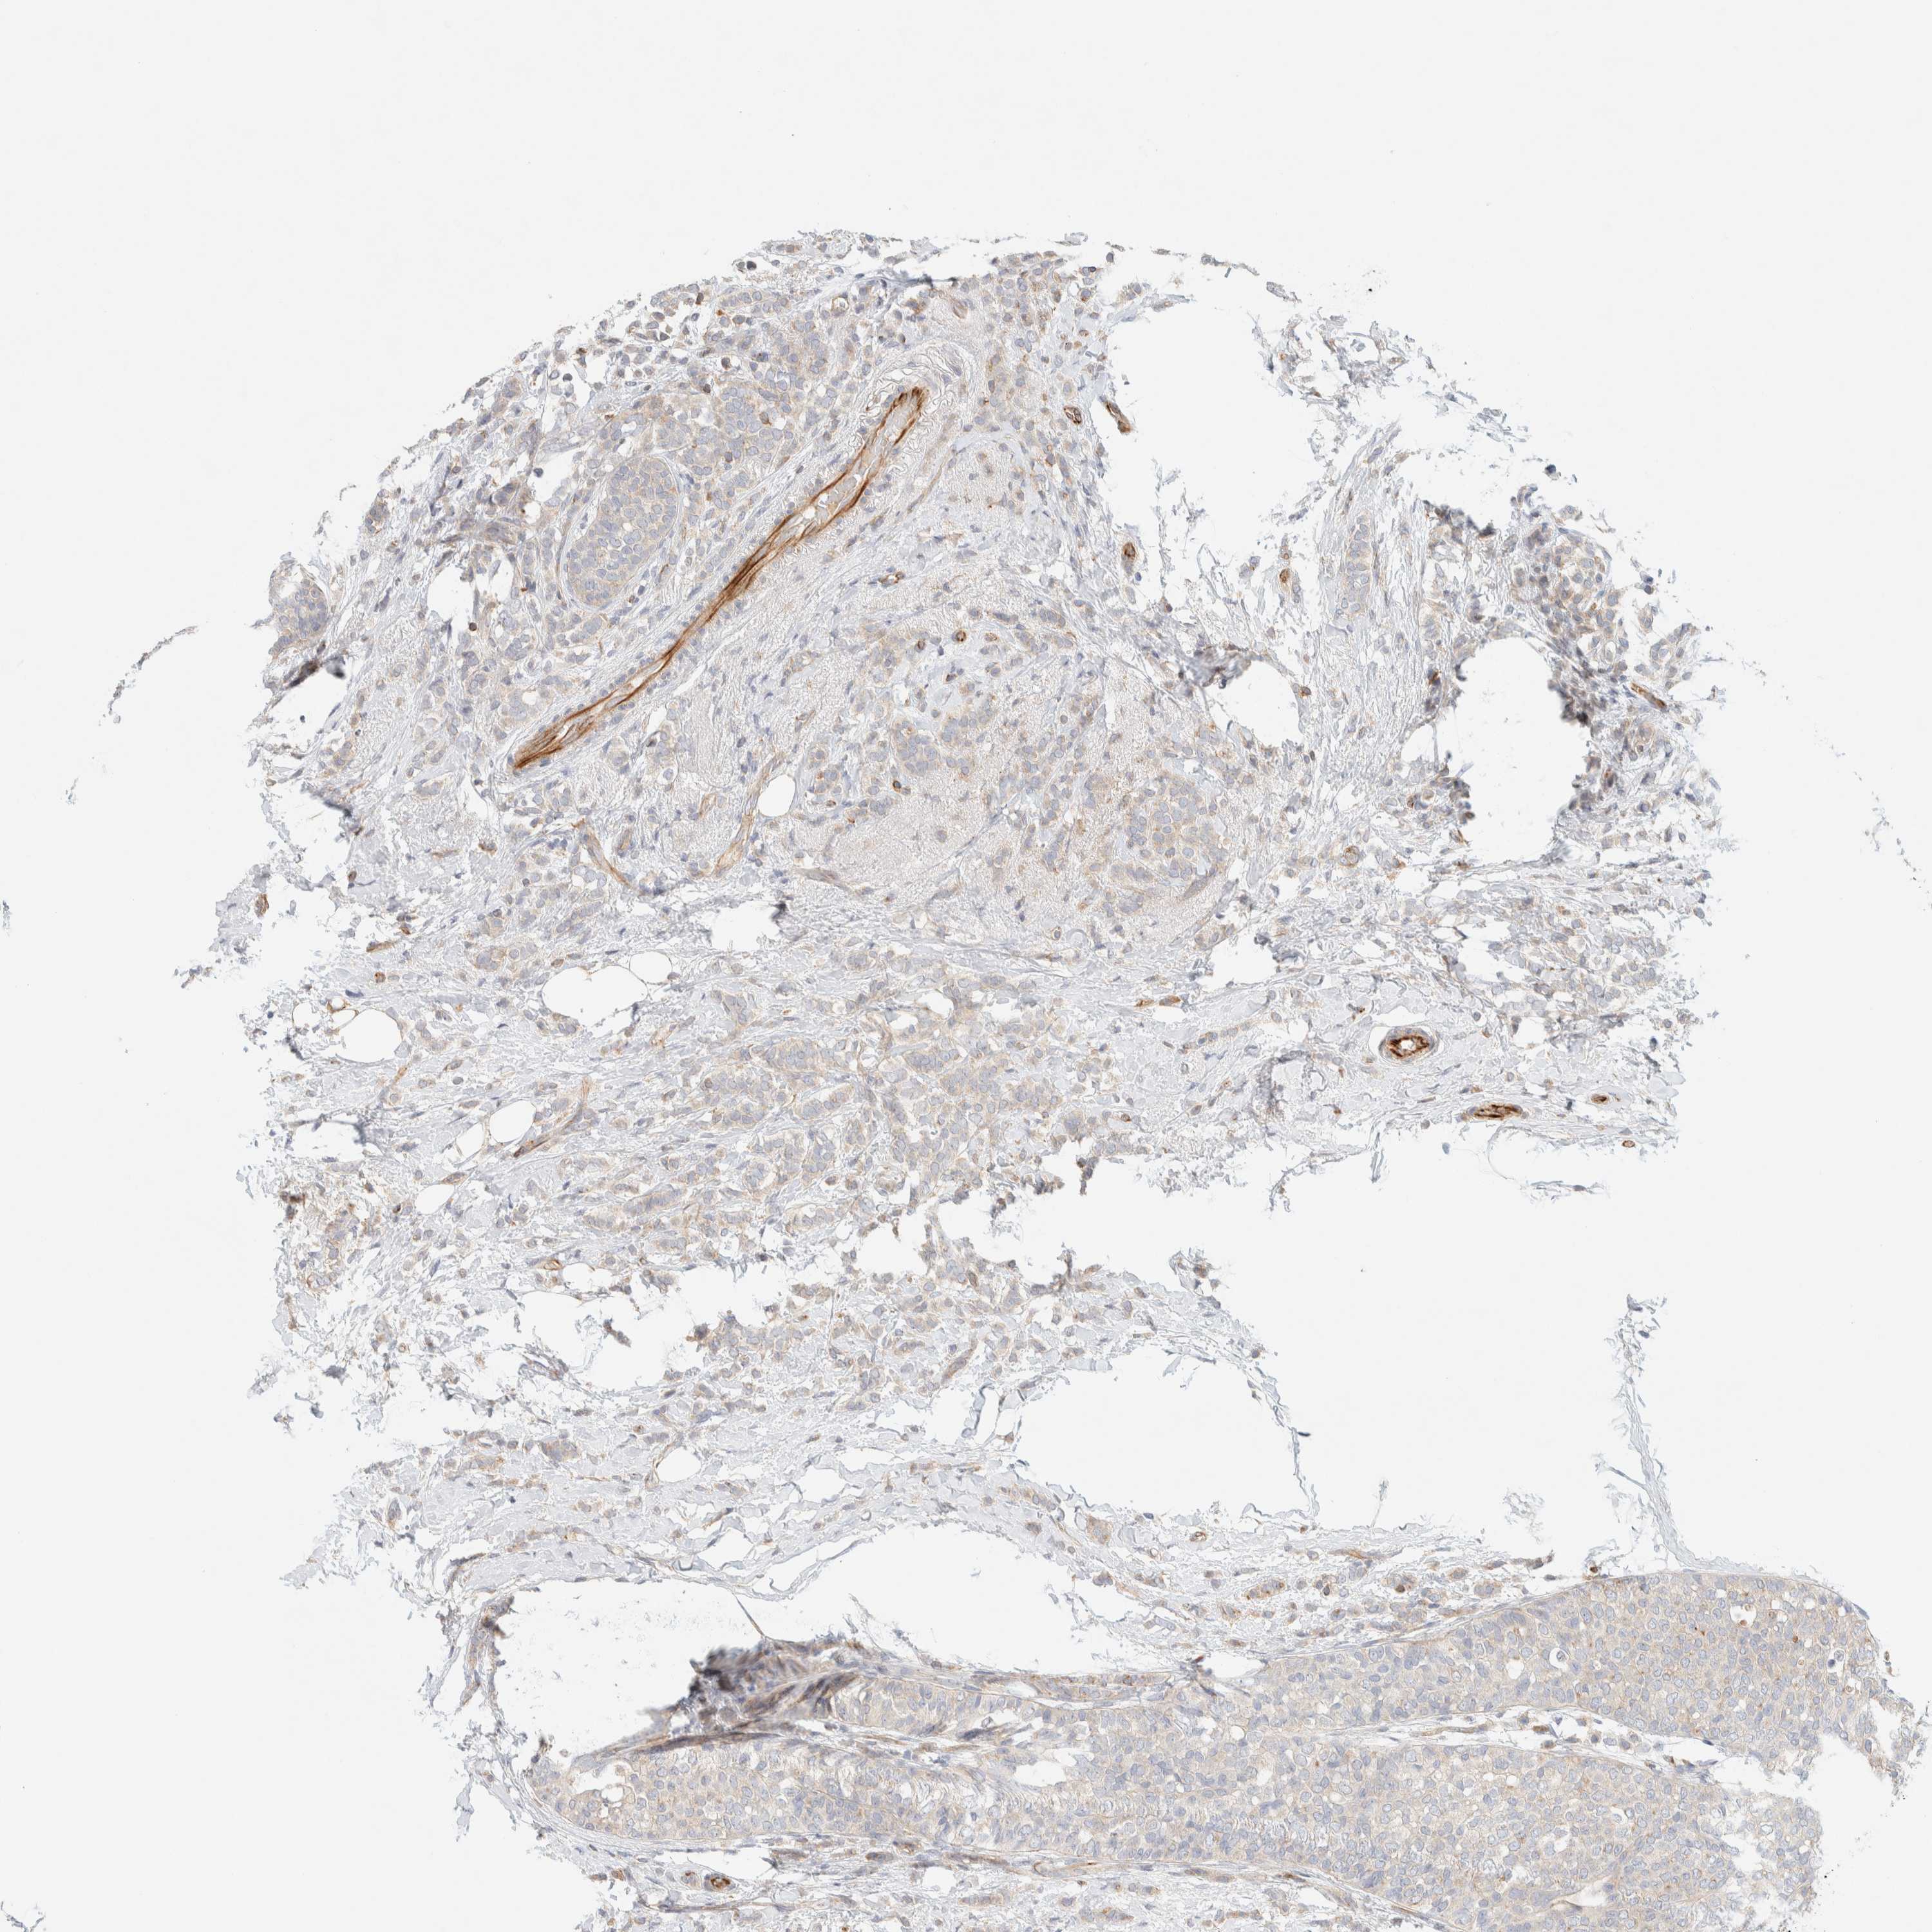

BRCA TCGA BRCA VALIDATION PROTEIN EXPRESSION

ANTIBODIES

AND

VALIDATION